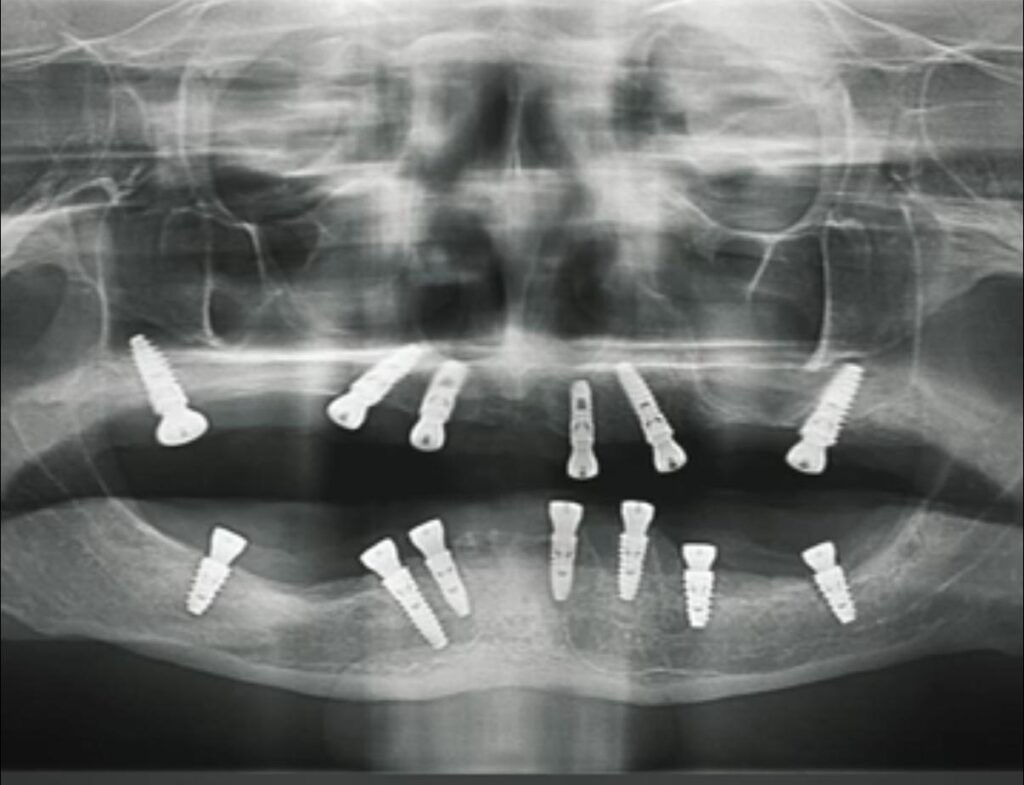

• Panoramic X-rays: These capture a panoramic view of the entire mouth, including the teeth, jaws, and surrounding structures. They are useful for assessing wisdom teeth, jaw disorders, and detecting tumors.

• Cone Beam Computed Tomography (CBCT): This advanced imaging technique produces detailed 3D images of the teeth, jawbone, nerve pathways, and soft tissues. It is commonly used for dental implant planning, orthodontic evaluation, and diagnosing complex dental issues.

OPG X-Ray